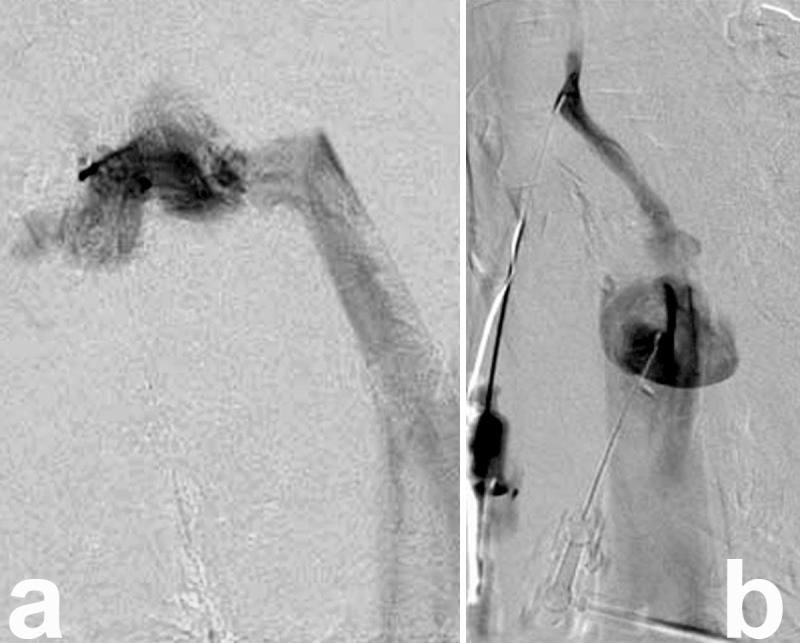

Venous malformations of the head and neck are congenital lesions that grow steadily without spontaneous regression. We describe the management of a 47-year-old woman with an extensive subcutaneous venous malformation of bilateral submandibular regions and the entire tongue, refractory to multiple surgical excisions and percutaneous sclerotherapy sessions. The tumour lacked prominent feeding arteries for embolisation, but maintained high blood outflow via a few substantial venous branches. Sclerotherapy to the lesion was prevented by major communicating branches from the mass to the internal jugular vein bilaterally. Our approach entailed direct surgical access to the malformation, ligation of these communicating veins and intraoperative sclerotherapy with ethanol injection into the vessel stumps.

头颈部静脉畸形是先天性病变,会持续生长且不会自发消退。我们描述了一名47岁女性的治疗过程,该患者双侧下颌下区域及整个舌头存在广泛的皮下静脉畸形,此前多次手术切除和经皮硬化治疗均无效。该肿瘤缺乏可用于栓塞的明显供血动脉,但通过一些粗大的静脉分支保持着较高的血液流出量。双侧从肿块至颈内静脉的主要交通支阻碍了对病变进行硬化治疗。我们的方法是直接手术暴露畸形,结扎这些交通静脉,并在术中进行硬化治疗,向血管残端注射乙醇。